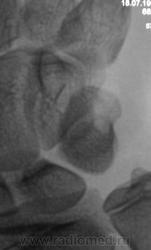

Пациентка направлена хирургом в рентгеновский кабинет для рентгенографии кисти и лучезапястного сустава. Вроде-бы, была и травма, после которой появилась боль в лучезапястном суставе.

перелом крючковидной кости, м.б и гороховидной (по поводу последней не очень уверен)

Укладки на трехгранную кость, она смещена каудально и радиально, структура неоднородная, но на счет перелома не уверена, а вот вывих трёхгранной кости есть.

Смущает перестройка структуры костной ткани, помечено стрелками.

Похоже на кисты (здесь - врождённые)

А может ГКО?